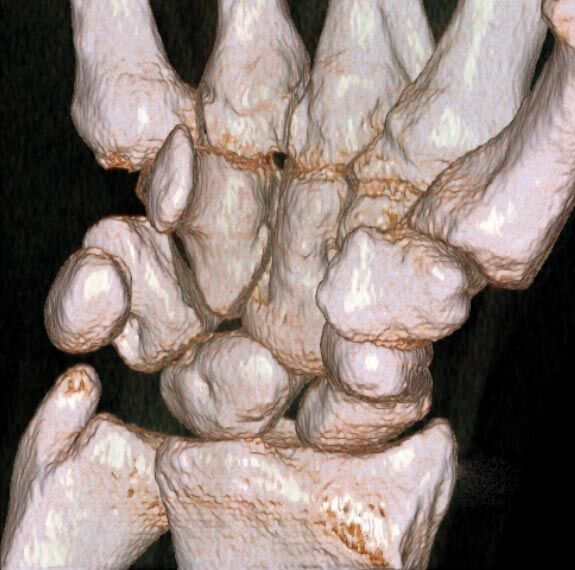

Extremitäten

• bei komplizierten Frakturen z. B. in der Nähe von Gelenken oder im Bereich der Handwurzel und Fußwurzel

• verbesserte Bildqualität bei Patienten mit Implantaten (z. Bsp. Hüftendoprothesen)

• besonders hochauflösende, strahlendosissparende Darstellung aller Skelettstrukturen